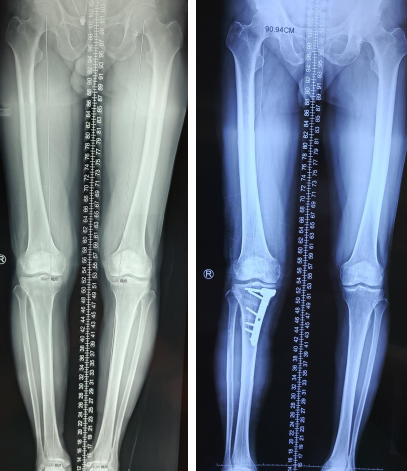

一年前,徐大爷因为右膝关节骨关节炎导致疼痛严重,各种保守治疗都没有效果,平时走路都十分困难,需要扶拐杖才能勉强下地走走,而且膝关节一点都不能下蹲,农村也没有马桶,上厕所都是个很大的麻烦事。当时,到徐州多家医院检查,医生要不建议徐大爷再忍忍,再试试别的保守方法,要不就是建议做全膝关节置换手术。徐大爷和家人一听说要把膝关节换成人工的,觉得是个大手术,都有些犹豫;后来从朋友那里打听到betway在线登陆有专门的保膝门诊,心想过来找个专家看看。每周三、周五正好是保膝专家邱东新医生出诊,邱医生仔细查看徐大爷的膝关节情况,结合拍摄的片子,认为徐大爷的膝关节症状虽然较重,但是关节磨损还没到晚期,完全可以做保膝手术。一听到可以保膝,徐大爷和家人虽然对于保膝理解不多,但很快接受,加上邱医生将保膝手术的过程、步骤、治疗的原理给徐大爷和家人进行了详细的讲解,徐大爷当即决定在必威官方首页官网betway住院,准备行保膝手术治疗。

一切都准备充足,手术在邱东新医生治疗小组的精心准备下顺利完成。徐大爷膝关节内自身所有结构都不做任何的破坏,仅仅通过在小腿骨上开一条骨缝,把腿矫正,并通过一个钢板来支撑就可以了。术后2天就能下地活动,术后一个月来门诊找邱医生复诊的时候,徐大爷已经能丢掉拐杖下地走路,疼痛明显减轻了。